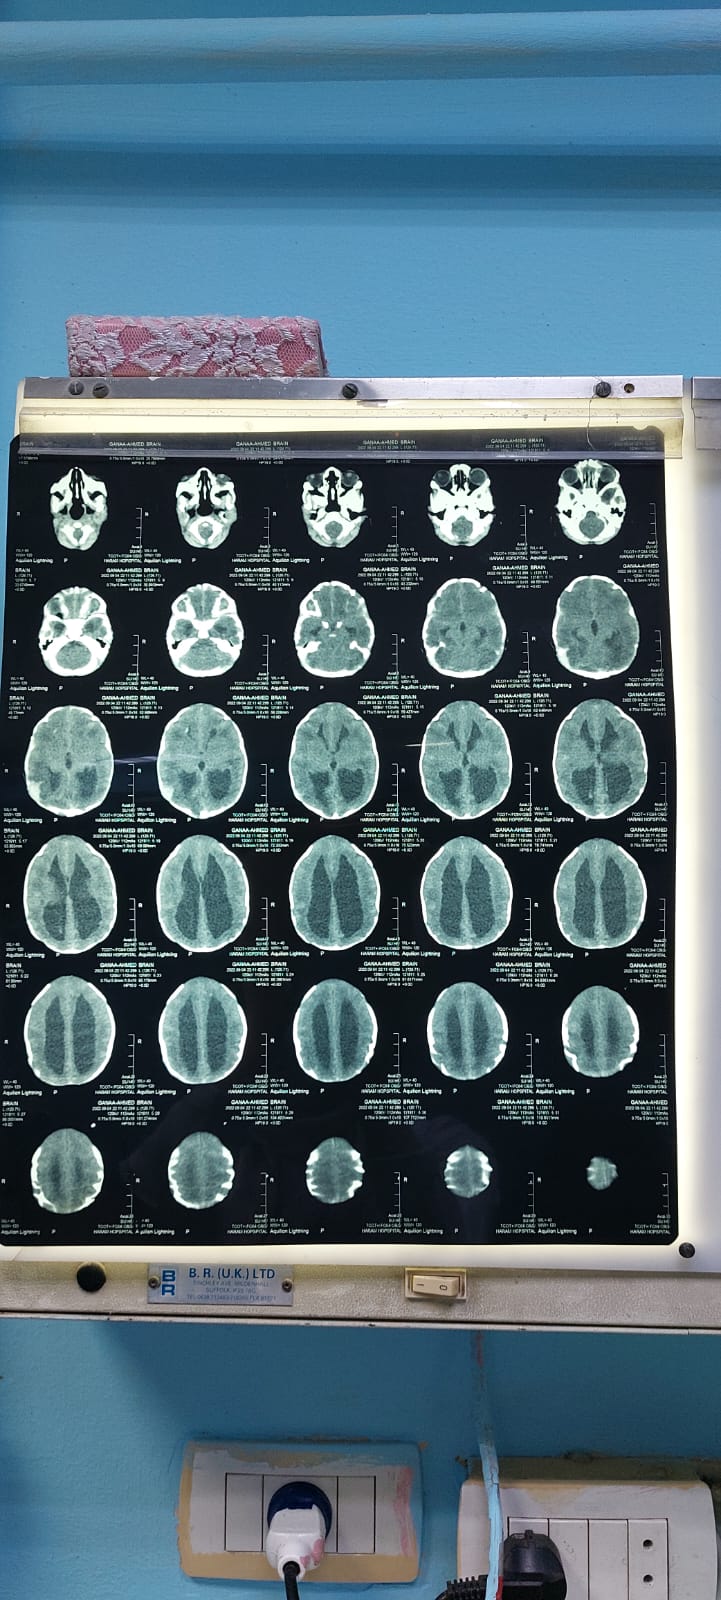

وواصل مجدي: عملت أشعة رنين وإيكو على القلب، ومقطعية، والدكاترة قالوا أنها محتاجة عملية جراحية ضروري، لأن الضفيرة العصبية للعمود الفقري غير مكتملة.

وقال الأب: احنا عرضنا الأشعة والتحاليل، على كذا دكتور كلهم قالوا لازم عمليه في المخ وعملية العمود الفق، متابعًا: في دكاترة قالوا لو عاشت كده هتعيش مشلولة.